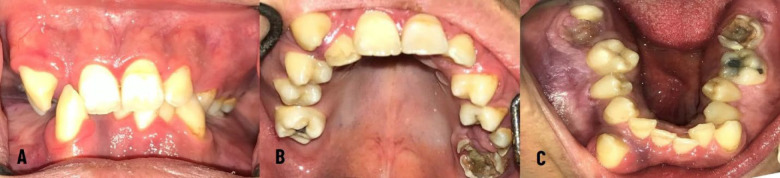

努南综合征是一种以各种系统性问题为特征的遗传病,包括心脏缺陷、身材矮小、出血问题和智力残疾。这种疾病也表现在口腔和颌面区域,突出了牙医在诊断和解决相关并发症中的作用。本报告描述了一名患有努南综合征的15岁男孩的有效牙科治疗,该男孩患有几种口腔和牙齿问题,在9个月的随访期间临床和放射学无症状。了解努南综合征患者的医疗状况和口腔面部表现可以有效地确定更好的治疗计划,提供更有效和更安全的治疗,并随后改善长期预后。

Noonan syndrome is a genetic condition characterized by various systemic issues, including cardiac defects, short stature, bleeding problems, and intellectual disabilities. This disorder also shows several manifestations in the oral and maxillofacial region, highlighting the dentist's role in diagnosing and addressing related complications. This report represents the effective dental management of a 15-year-old boy with Noonan syndrome who suffered from several oral and dental problems and was clinically and radiographically asymptomatic in a nine-month follow-up session. Awareness of the medical conditions and orofacial manifestations of patients with Noonan syndrome can be effective in determining a better treatment plan, providing more effective and safer treatment, and subsequently enhancing the long-term prognosis.